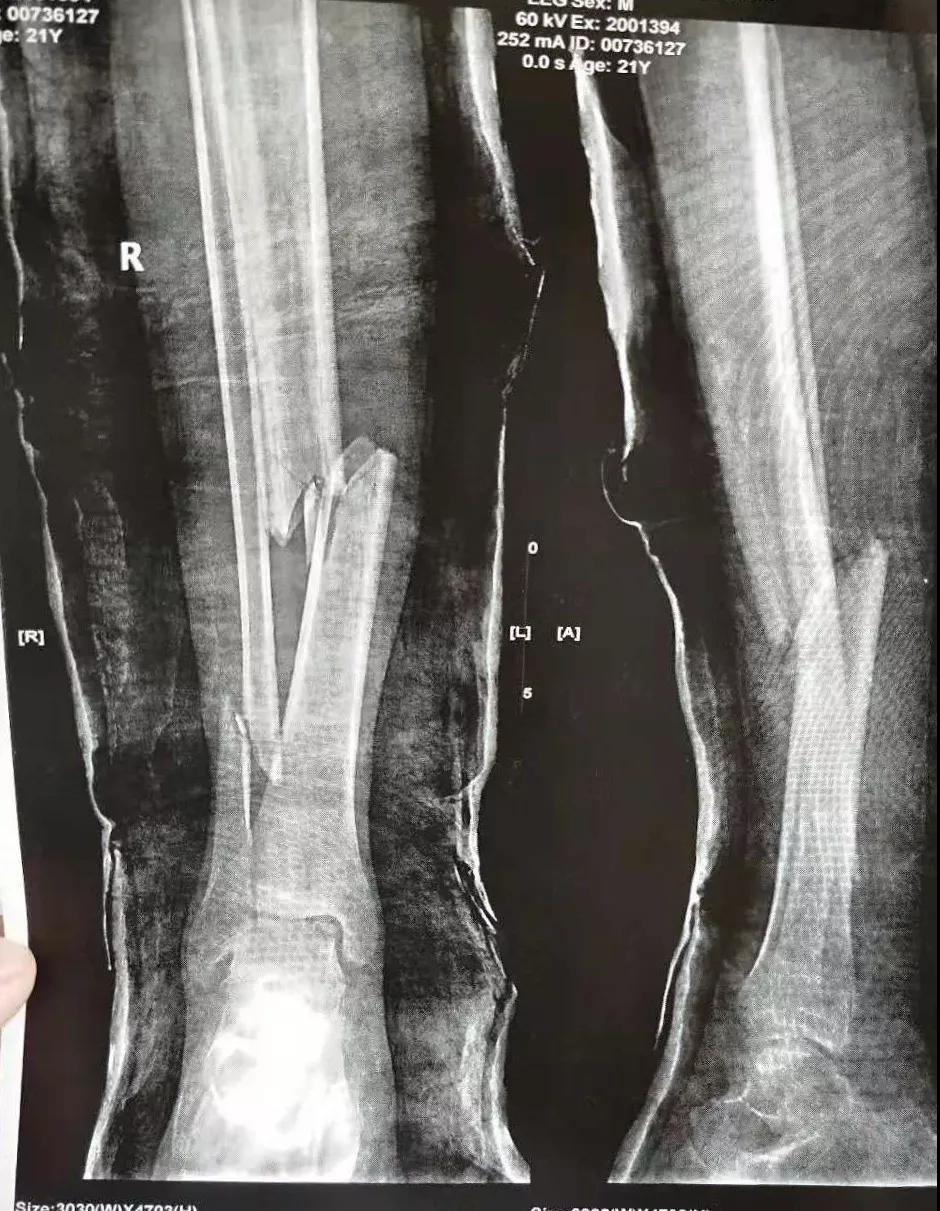

这名21岁的男性患者一个月前因车祸致伤,在当地某三甲医院确诊为右胫腓骨粉碎性骨折,骨折移位明显,建议手术治疗,因既往患严重慢性再生障碍性贫血病史16年,一般状况差,需长期输注血液制品维持三系细胞水平,麻醉及手术风险极高。虽经当地积极内科治疗,患者一般状况仍差,无法耐受手术治疗。患者及家属经多方打听,抱着最后一丝希望来到六合彩生肖骨二科求治。

骨二科张延平主任接诊后经仔细询问病史,详细阅读近期X线、CT等病历资料,认为患者骨折移位明显,目前骨折无任何愈合迹象,若保守治疗,骨折将无法愈合,后期不能下地活动,严重影响患者生活质量。同时患者合并慢性再障,血常规结果各项指标均极低,围术期发生麻醉意外、大出血、感染等风险极高;而六合彩生肖作为西安市级最大的三甲综合医院,综合实力深厚,既往相关疾病治疗经验丰富,多次通过多学科诊治为合并复杂内科疾病患者保驾护航,为患者创造手术时机,提高患者生活质量,遂将患者收住院。住院后,立即成立了由张延平主任、杨寅副主任、山卉护士长、梁晨主治医师、刘邦定主治医师、李鑫护师组成的手术治疗小组。经初步检查,患者血常规结果较当地检验结果更差,三系细胞均极低,其中血小板仅为1(正常值为100-300),血红蛋白55g/L。遂立即请血研所李罡灿主任医师会诊,给予升高白细胞、纠正贫血、升高血小板等治疗,经积极治疗患者血常规各项指标均较入院时改善。张延平主任再次组织由血研所李罡灿主任医师、麻醉科崔晓岗主任、感染科付建军主任、药剂科韩小年副主任药师等参加的术前讨论。讨论后一致认为患者目前各项指标虽然较入院时改善,但因其慢性再障病史长,骨髓造血及储备能力极差,围术期发生大出血、伤口感染甚至全身感染等风险仍极高,术中及术后需准备大量血小板防止大出血,同时需高度警惕手术切口、取骨区术后发生感染。为尽快为患者施行手术,治疗小组积极联系输血科为患者备血,并为患者制定了围术期抗感染方案;在六合彩生肖输血科存血量严重不足的状态时,输血科张养民主任亲自联系市中心血站为患者准备手术中及术后所需的血小板制品。手术小组为患者制定了周密的手术方案及风险预案,10月31日,在麻醉科王永宏副主任医师、手术室高洁、赵耀护师的配合下,为患者施行了右胫骨粉碎性骨折切开复位、髂骨取骨植骨内固定术,手术历时70分钟,安全返回病房。术后患者渗血多,1周内连续每日平均渗血超过100ml,并出现发烧,最高39℃,复查血常规三系细胞较术前再次明显降低。李罡灿主任医师、付建军主任、韩小年副主任药师多次来科会诊,及时调整患者的治疗方案,输血科再次为患者的救治提供了强有力的支援和保障。在山卉护士长带领的护理团队精心护理下,患者未发生压疮等卧床并发症。目前该患者术后恢复良好,已出院进行下一步康复治疗。